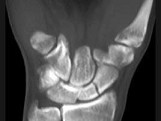

- 单项选择题男,21岁, 手部不慎摔伤,局部疼痛, 结合图像,最可能的诊断是 ( )

A、大多角骨骨折

B、小多角骨骨折

C、三角骨骨折

D、月骨骨折

E、舟状骨骨折